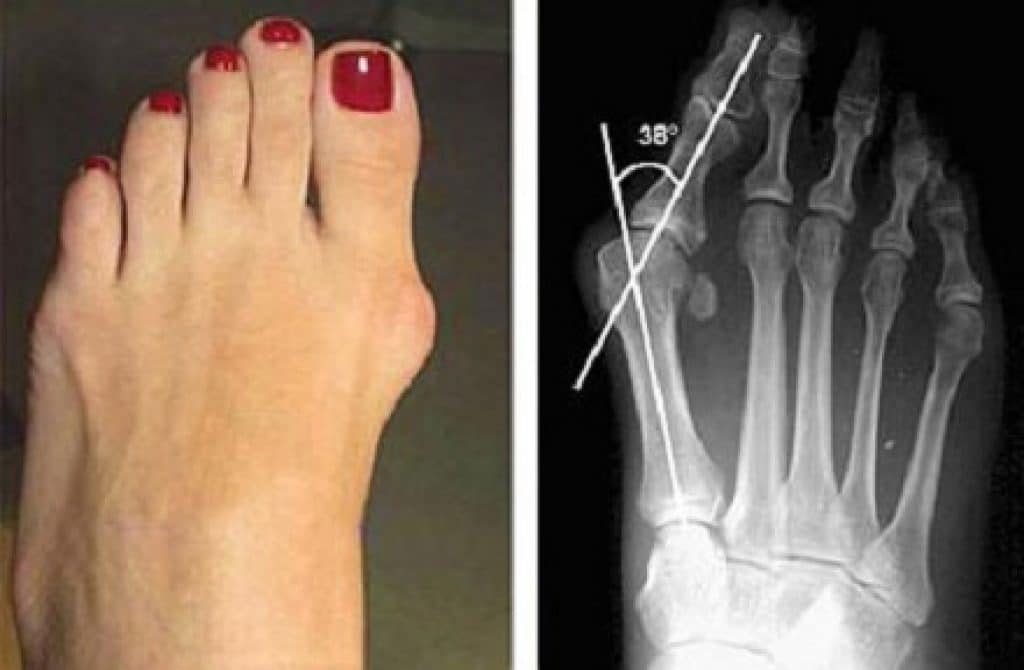

Вальгусная Деформация Стопы Фото После Операции

Вальгусная Деформация Стопы Фото После Операции 110 фото